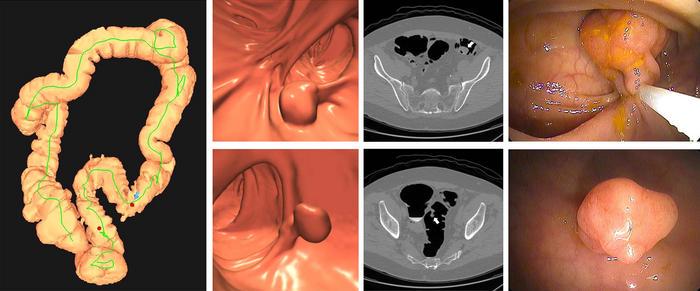

Colorectal cancer often develops from precancerous polyps, which remain asymptomatic for years before progressing to invasive malignancies. Early identification and removal of these polyps are pivotal in disrupting this progression chain. Optical colonoscopy has long been the gold standard due to its ability to not only visualize but also resect lesions during a single procedure. However, colonoscopy’s invasive nature, bowel preparation demands, and relatively high cost have spurred the development and Medicare endorsement of alternative screening techniques. Among these, mt-sDNA testing analyzes fecal samples for genomic and epigenomic biomarkers indicative of neoplastic changes, while CT colonography non-invasively images the entirety of the colon and rectum using computed tomography.

Image Credits: Radiological Society of North America (RSNA)